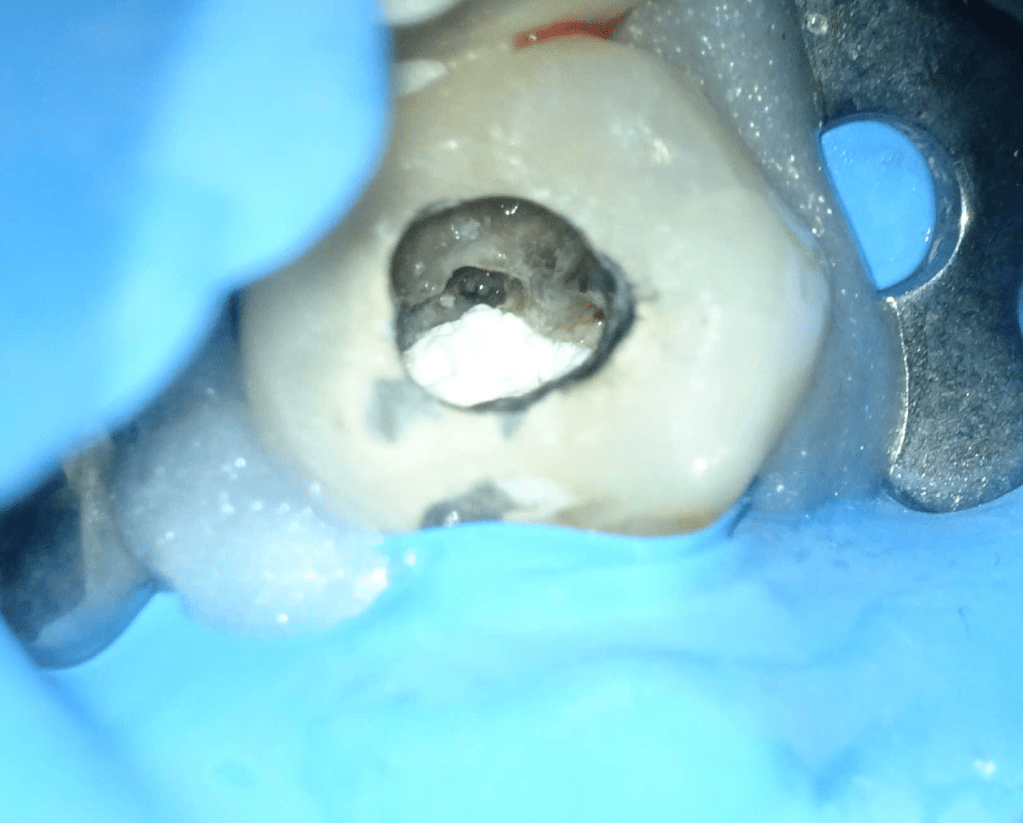

Reco pared vesticular

Reco pared vesticular